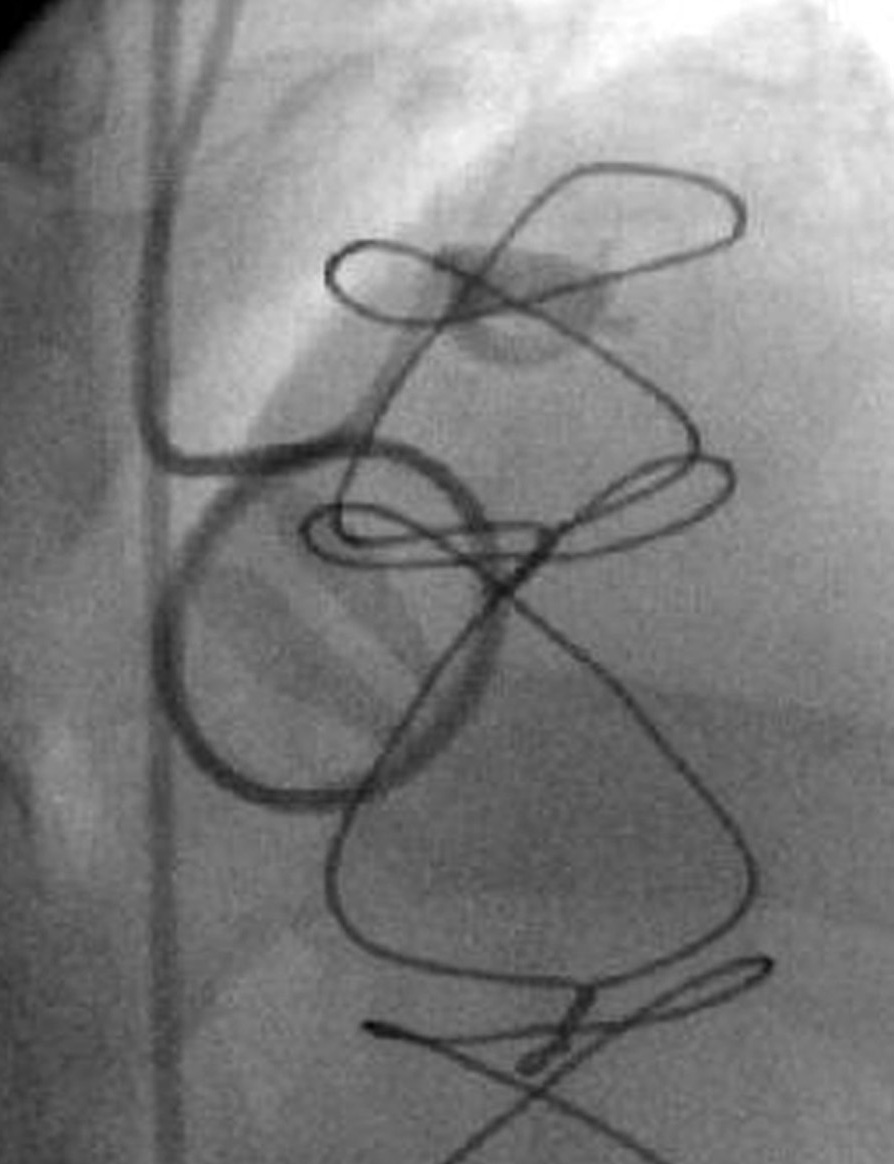

We present a case of an acute myocardial infarction with ST segment elevation in a patient with a mechanical aortic valve prosthesis who had discontinued anticoagulant therapy. We performed a primary coronary intervention procedure, including thrombus aspiration as well as plain balloon angioplasty (low atmospheres), in order to restore coronary flow in left anterior descending artery as soon as possible. Review of the literature suggests that in such cases the diagnosis of the embolic origin of the acute coronary syndrome is assumed and can never been proved definitely. Thrombus aspiration must be included in the therapeutic strategy of these patients.